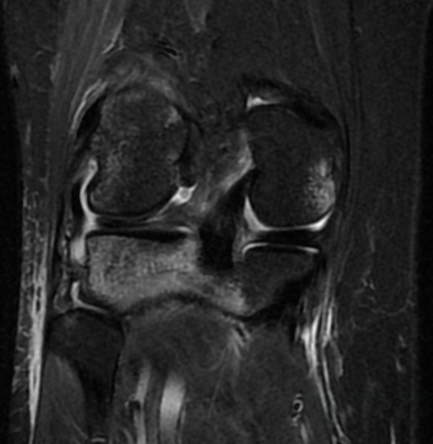

Pop Goes the Knee Author: Tyler Jackson, MD, CAQ-SM Peer-reviewer: Terese Whipple, MD, CAQ-SM Final editor: Alex Tomesch, MD, CAQ-SM A 25-year-old male presents with right knee pain after a bicycle accident in which his knee twisted after planting his foot while falling off the bicycle. He also reports his knee occasionally “locks” when trying to ambulate since the injury. ROM is restricted with knee extension and flexion. Image 1 and 2. MRI R Knee (Sagittal and Axial PD) Case courtesy of Dr. Varun Babu, Radiopaedia.org, rID: 56916 References: [1][ Chambers HG, Chambers RC: The natural history of meniscus tears . J Pediatr Orthop. 2019, 39:53-5. [2] Jarraya M, Roemer FW, Englund M, et al.: Meniscus morphology: does tear type matter? A narrative review with focus on relevance for osteoarthritis research. Semin Arthritis Rheum. 2017, 46:552-61. [3] Esparragoza-Montero R, Rodriguez-Diaz J, Lanier- Dominguez J, et al. Evaluation of meniscal morphology and relation between the diagnostic findings of magnetic resonance imaging and arthroscopy in lesions of the knee. Invest Clin 2009;50(1): 35-44.